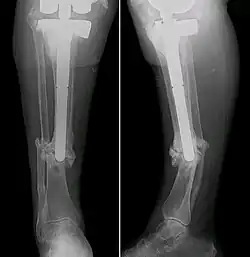

Intramedullary stabilization involves inserting a rod or nail into the tibial medullary canal. This offers structural support from within the affected bone, allowing for bone alignment and union. Surgeons may opt for flexible or rigid intramedullary nails depending on patient-specific factors such as age, pseudarthrosis severity and any accompanying deformities.[28] Although it almost guaranteed fracture healing and no refractures within a few years, the intramedullary nails would need to be replaced with age, leading to the pain of repeated surgery.[29][30][31]

Ilizarov fixation is an effective surgical approach for treating CPT, particularly when significant bone gaps or deformities are present. The technique involves applying an external fixator framework known as an Ilizarov apparatus. Composed of rings connected by wires and thin wires or half-pins inserted into the bone, the apparatus allows precise control over bone alignment by gradually distracting or compressing bone ends.[24] Through application of regulated forces, the Ilizarov method stimulates new bone formation and facilitates bone union. Steady adjustments to the frame can progressively correct deformities, lengthen the bone, and induce consolidation across the pseudarthrosis site.[25] This technique has been proven to have high healing rate and a low refracture rate later on in clinical practice.[26][25]

In cases of extensive tibial bone loss or compromised blood flow, surgeons may perform a free vascularized fibular graft. This involves harvesting a section of fibula (usually 10–12 cm long) along with its blood supply from the patient's leg and transplanting it to the pseudarthrosis site.[32] As a vascularized graft, the fibula provides a fresh blood source to aid bone growth and repair at the defect location.[33] This unconventional procedure is reserved for the most challenging clinical presentations, saving many children with CPT from amputation since it was invented in the 1990s.[34] However, due to the lack of mechanical support, the healed bone has a high chance of refracture if this technique was applied alone for CPT treatment.[35] Therefore, it is commonly applied together with intramedullary nails in recent years so as to deal with both tibial loss and low bone mechanical strength, and has demonstrated satisfying efficacy in clinical practice.[36][37]